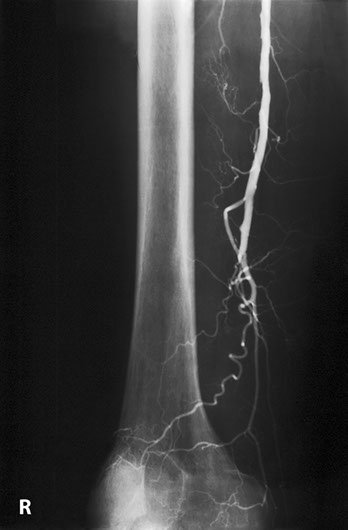

This patient developed several strictures two years apart. This one is a popliteal stricture.

Popliteal stricture post dilatation

And this represents the second stricture two years later in the left lower femoral artery

And this is the post-dilatation image of the femoral stricture.